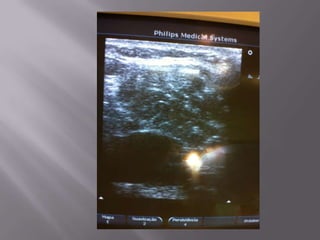

EVIDÊNCIA ROBUSTA -> Menos complicações, menos tentativas, menor tempo para o procedimento  Só é possível saber o paciente difícil de puncionar após tentativa frustrada  Tentativas frustradas chegam a 14-20% no acesso jugular e 15-40% no acesso femural.  Permite escolher a melhor veia para punção ( ÓBVIO!!!!!!!!!!!!)